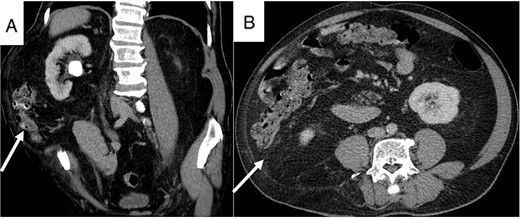

A 74-year-old male presented to our hospital with persistent right flank pain for 5 months who had undergone previous open nephrolithotomy to treat a staghorn stone 10 years ago. He was classified ASA class III due to moderate heart failure, characterized by a 40% ejection fraction. Physical examination revealed a bulky mass on the right lumbar region lateral to the anterior axillary line, consistent with CT scan findings (Fig. 3). A 27 mm stone was observed in the right ureteropelvic junction (UPJ).

Patient’s CT scan shows right UPJ stone (A) and lumbar hernia with mesentery inside (A and B, arrow).